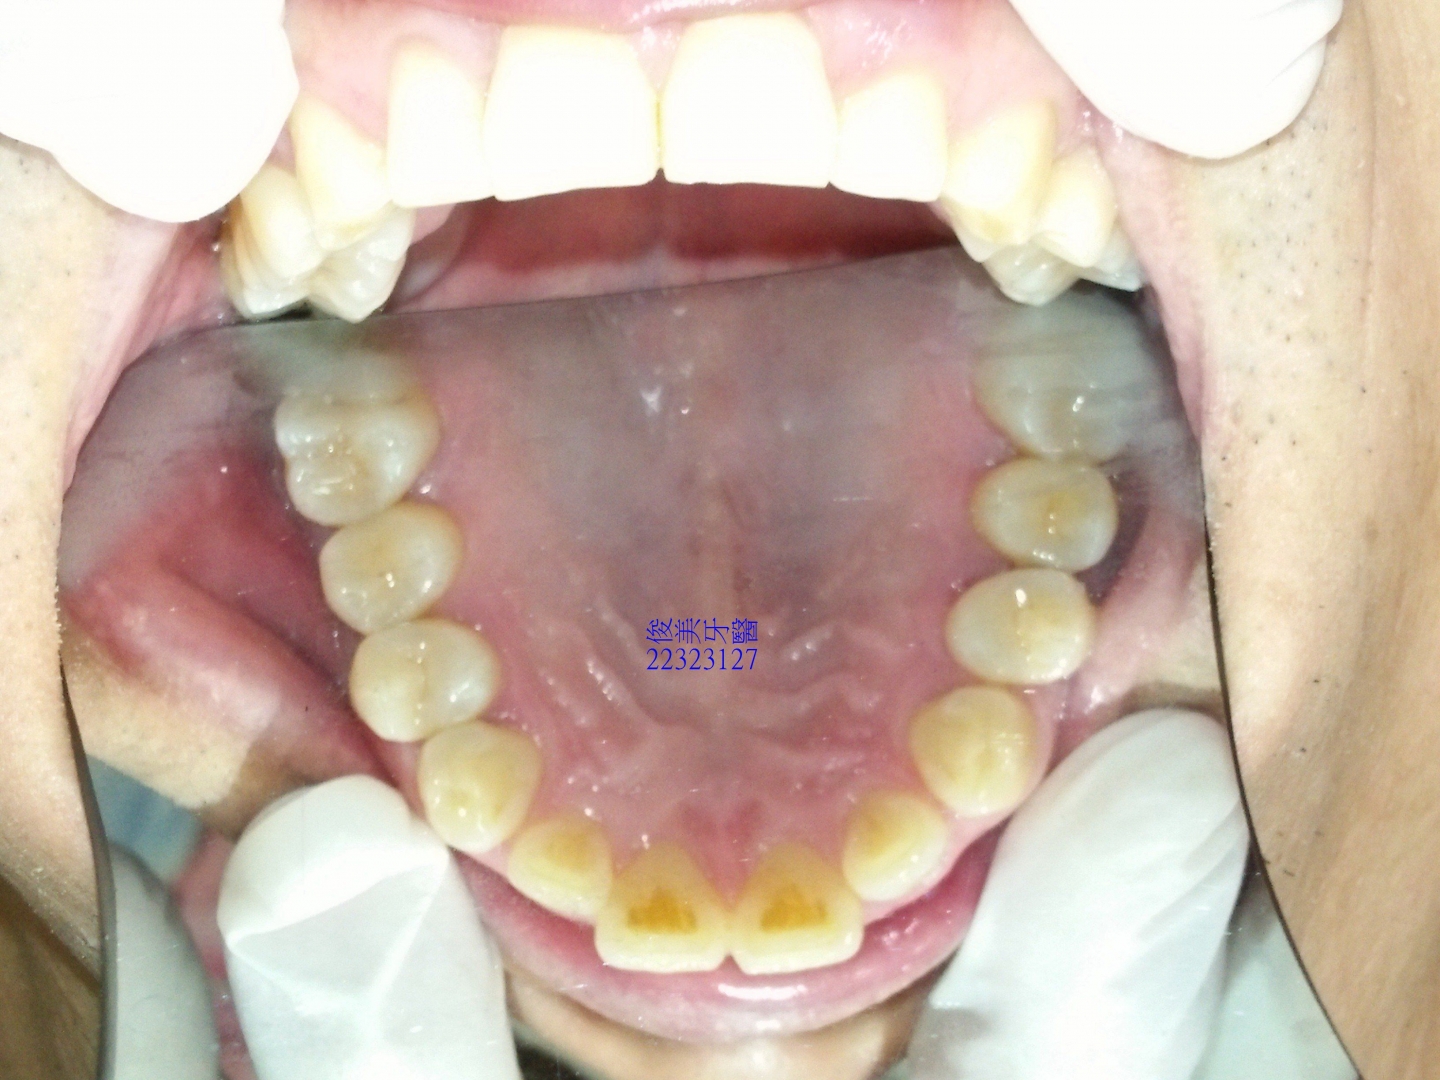

下顎原始狀況。牙齒開始內傾到舌側位置。

後牙咬合高度逐漸變低。

後牙咬合高度逐漸變低;犬齒受力大,高度剩下2/3,切端皆已磨損喪失。